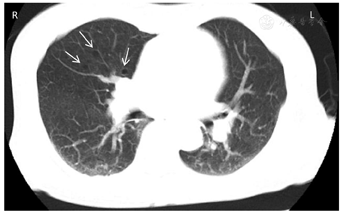

腹部彩超:多囊肾声像图改变;双肾结石;双侧输尿管无扩张;肝内实性病灶;肝多发囊肿;胆胰脾未见明显异常。心电图及心脏彩超未见明显异常。全腹部CT平扫(图1):双肾改变,考虑多囊肾、部分为复杂囊肿,合并多发错构瘤,以左肾为显著;肝内多发低密度灶,囊肿。胸部CT平扫(图2):双肺多发囊腔,考虑肺淋巴管肌瘤。胸椎及肋骨多发结节状高密度灶。头颅MRI平扫(图3):双侧额叶、左侧顶叶、右侧颞叶皮质及皮质下结节状异常信号。

由于TSC1、TSC2基因突变导致TSC合并多囊肾的发病率也明显高于普通人群。2012年国际结节性硬化症共识会议对TSC诊断标准进行了修订[1],将基因检测列为独立的诊断标准,通过基因检测可鉴定出TSC1或TSC2致病突变即可确诊TSC。15%~25%的TSC患者通过常规基因检测未能检出突变,故基因检测阴性不能排除TSC,亦不作为TSC诊断金标准。当临床诊断疑似时可行基因诊断。临床诊断标准包括:主要特征:(1)色素脱失斑(≥3个,直径≥5 mm);(2)面部血管纤维瘤(≥3个)或头部纤维性斑块;(3)甲周纤维瘤(≥2个);(4)鲨革斑;(5)多发性视网膜错构瘤;(6)脑皮质发育不良(包括结节和脑白质辐射状迁移线);(7)室管膜下结节;(8)室管膜下巨细胞星形细胞瘤;(9)心脏横纹肌瘤;(10)肺淋巴管肌瘤病;(11)肾脏血管平滑肌脂肪瘤(肾错构瘤)。次要特征:(1)"斑驳状"皮肤改变;(2)牙釉质点状凹陷(≥3个);(3)口腔内纤维瘤(≥2);(4)视网膜色素缺失斑;(5)多发肾囊肿;(6)非肾脏错构瘤。具有2个主要特征,或1个主要特征加2个次要特征可确诊;具有1个主要特征,或1个主要特征加1个次要特征,或≥2个次要特征为疑似。

TSC可累及多脏器多系统,根据发病年龄受累器官不同,其临床表现也不尽相同。有学者将其主要临床表现归纳为血管纤维瘤、癫痫发作及智力减退三联征。本例患者无上述临床表现,诊断上易出现误诊、漏诊。本例患者TSC诊断得益于腹部、胸部及头颅影像学对各系统检查提示:同时具有多个肾错构瘤、肺淋巴管肌瘤、大脑皮质及皮质下多发结节3个主要特征及多发肾囊肿1个次要特征。患者目前规律随访中,病情无进展。根据2012年TSC专家共识院外仍需定期进行腹部及头颅影像学检查,及对肾小球滤过率及血压进行定期评估。TSC为常染色体显性遗传,疾病根据个体发育阶段的不同而有不同发展。患者儿子患多囊肾,进一步腹部、头部影像学检查有助于排查有无脏器受累。基因检测亦可用于遗传咨询或诊断不明确情况下。